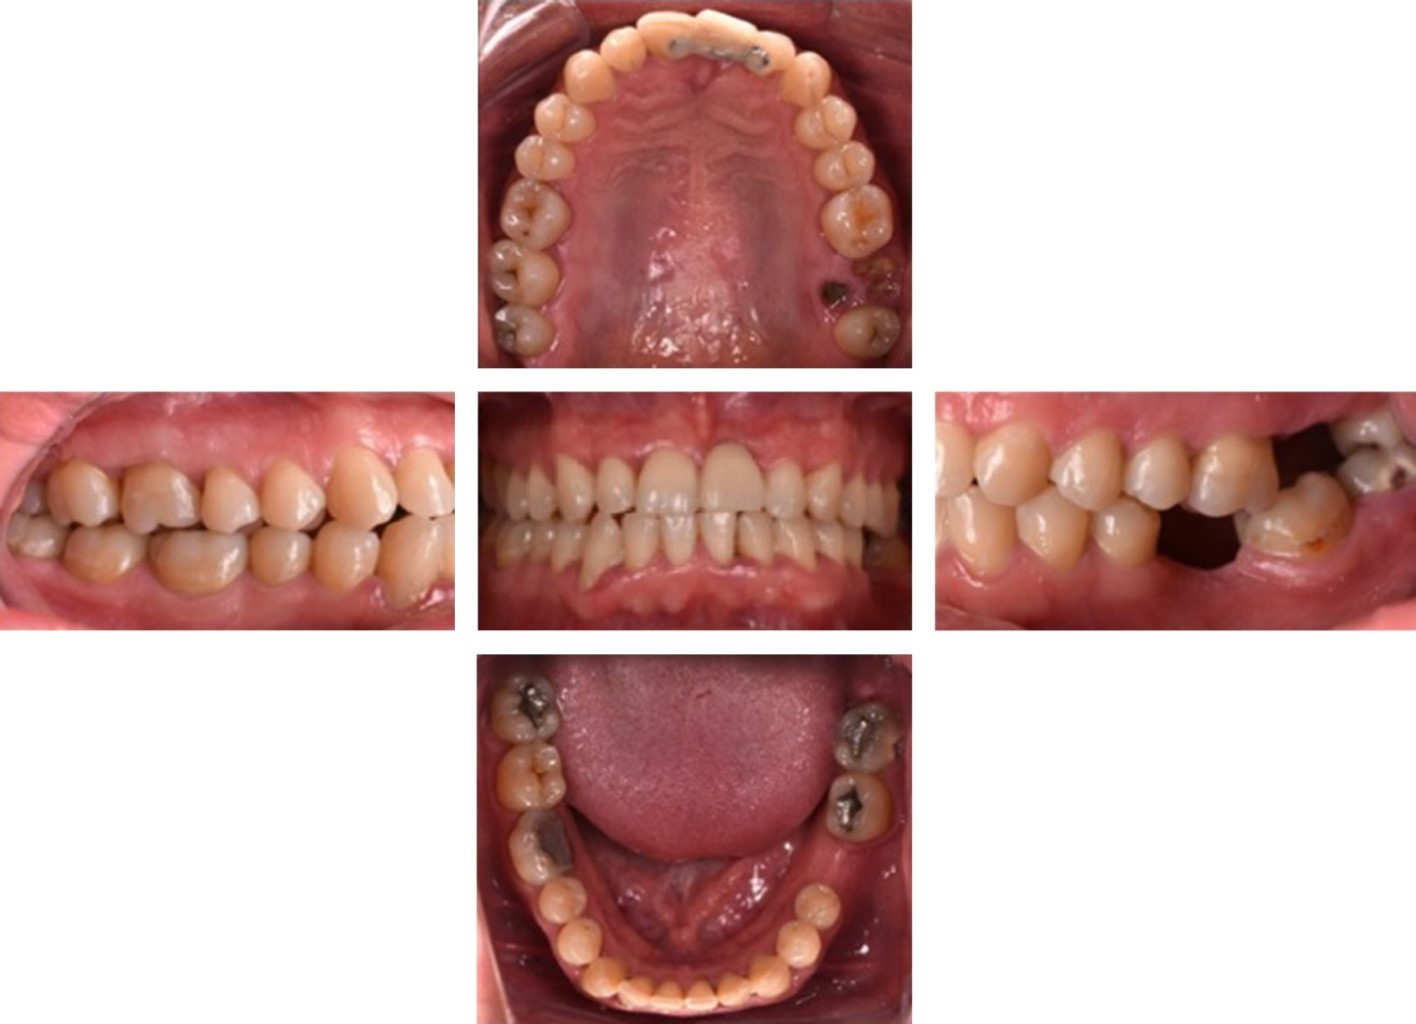

Intraoral examination showed incipient carious lesions in the occlusal surfaces of teeth 14, 15, 24, 25, 26, 34, 35, and 44; brown pigmentation in occlusal surfaces compatible with enamel caries in molars 16, 17, 18, 28, and 47; brown pigmentation with cavitation in the cervical area of the buccal surface of molar 38 compatible with caries in dentin; root fragments in the area of molar 27; dental amalgams in the occlusal faces of molars 37, 38, 46 and 48; plaque and generalized calculus; generalized gingival inflammation; absence of molar 36; a provisional fixed partial prosthesis adhered with orthodontic wire in the region of tooth 21. In this area, we observed a Seibert class III defect and a Benic and Hämmerle class III as mentioned by Benic and Hämmerle, and Seibert1,12 (Figure 2).

The orthopantomography analysis confirmed the absence of teeth 21 and 36 as well as the presence of root fragments of molar 27 and a defective restoration in 38 (Figure 3). The study models analysis, mounted in a semi-adjustable articulator, revealed a discrepancy between centric relation and maximum intercuspation records (Figure 4A-B).

Figure 2

Figure 4